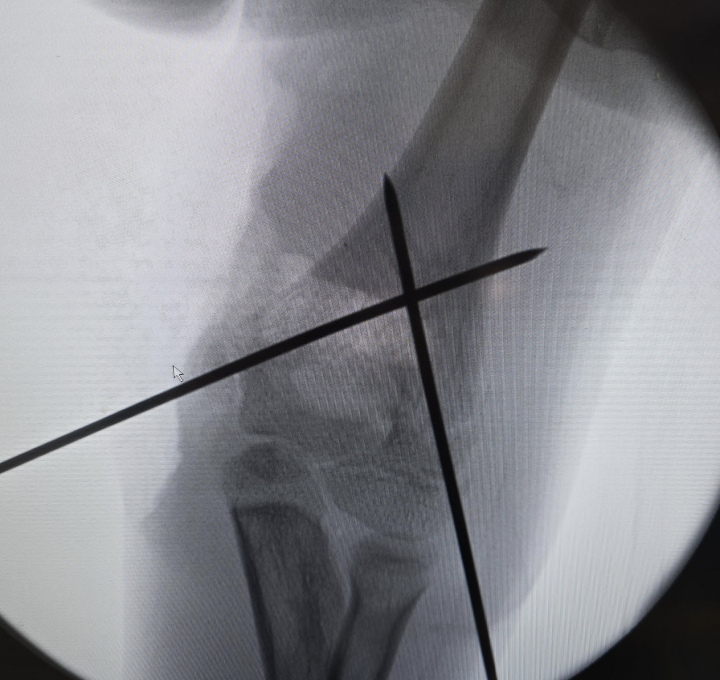

Fractures de l'Enfant